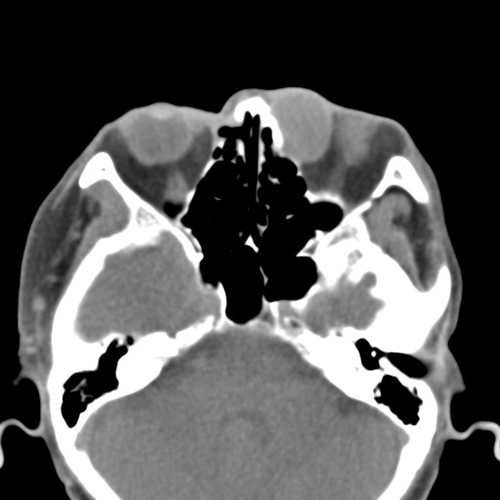

眼科副主任朱晓宇介绍,该患者为老年女性,自2年前发现左眼眶缘肿块后,肿块开始渐进性向眶内增长,并出现明显复视。患者随即来我院眼科门诊就诊,经眼眶CT后检查发现,肿块已累及眼眶,经过入院前评估,患者被收入日间病房。